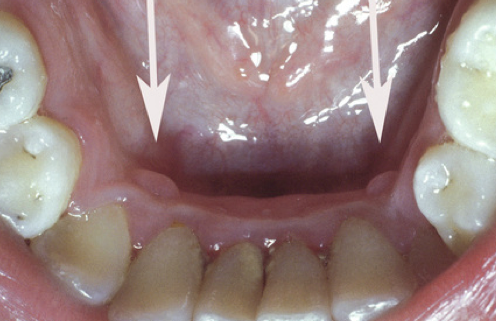

What is the likely Dx?

Giant cell fibroma.